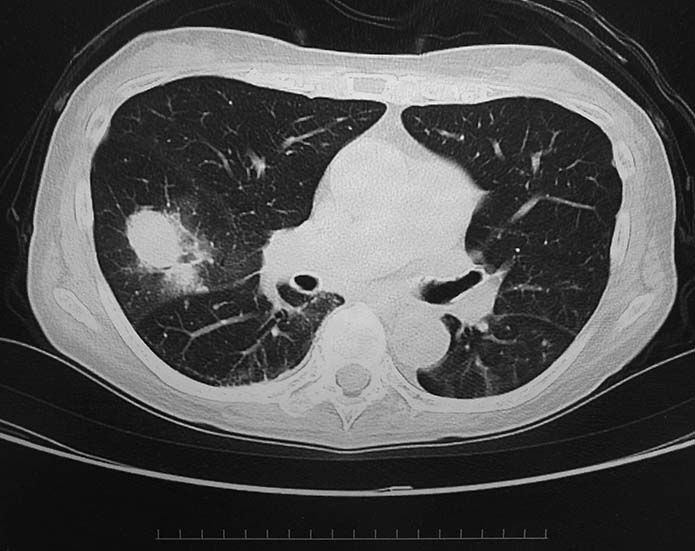

• X線検査では,通常,両肺の中・下部領域に多数の空洞化した転移性結節が認められる. 肺外への浸潤は極めて稀. 皮膚,中枢神経系,肝臓,腎臓などにも転移が見られる.

今月定期受診で1年ぶりにchest X-pを撮影. 両肺野に多発結節影が指摘されて受診となった.

chestX-pとCT.サムネイル画像クリックで大きな画像がみられます.